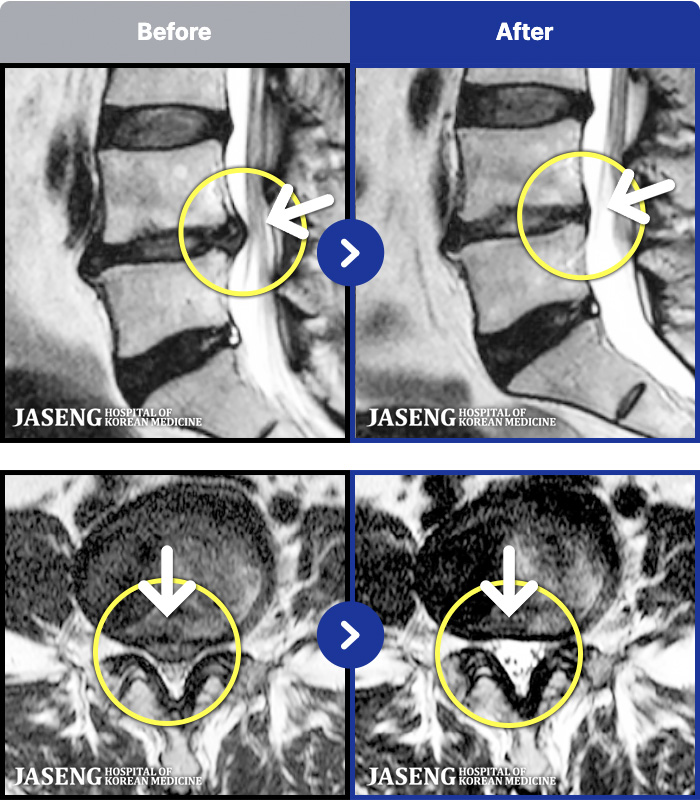

1,296 MRI ũ ʸ Ȯϼ.

[] 23.11.11~25.06.04